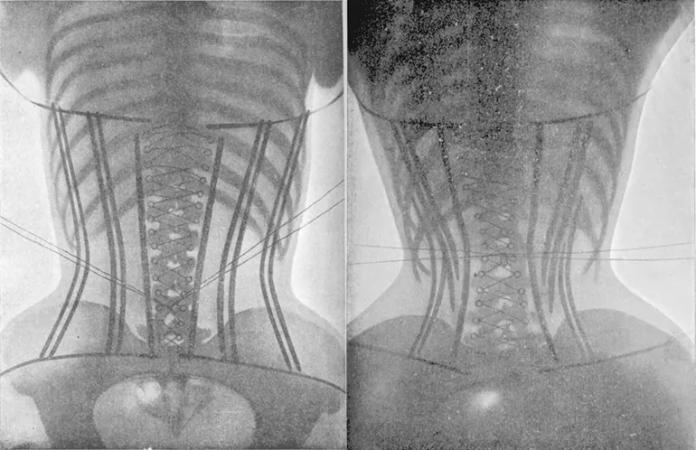

Incluso hace ilustraciones anatómicas para ver la severidad de lo que puede causar esta práctica:

funcionan las fajas colombianas

Como se puede ver, las costillas quedan tan estrechas que se dificulta la respiración.

Esto también se ha podido ver con tecnología de rayos x:

fajas colombianas reductoras efectos secundarios